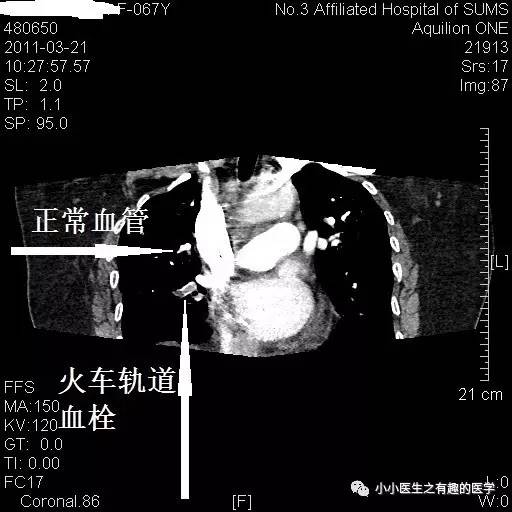

病例一:

女性,老年,胸痛伴气喘20余天。1周前出现双下肢浮肿。查体:双下肢足背浮肿。D-二聚体:5.10 ug/mL。心脏彩超:肺动脉收缩压RVSP:39mmHg。B超:双下肢深静脉血栓形成。

左肺动脉血栓。

左侧血栓,对比右侧就很通畅,一路顺风。

这条公路,全程阻塞,后方车辆请绕行。

小血栓。

右边也有血栓。

最终诊断:肺栓塞。